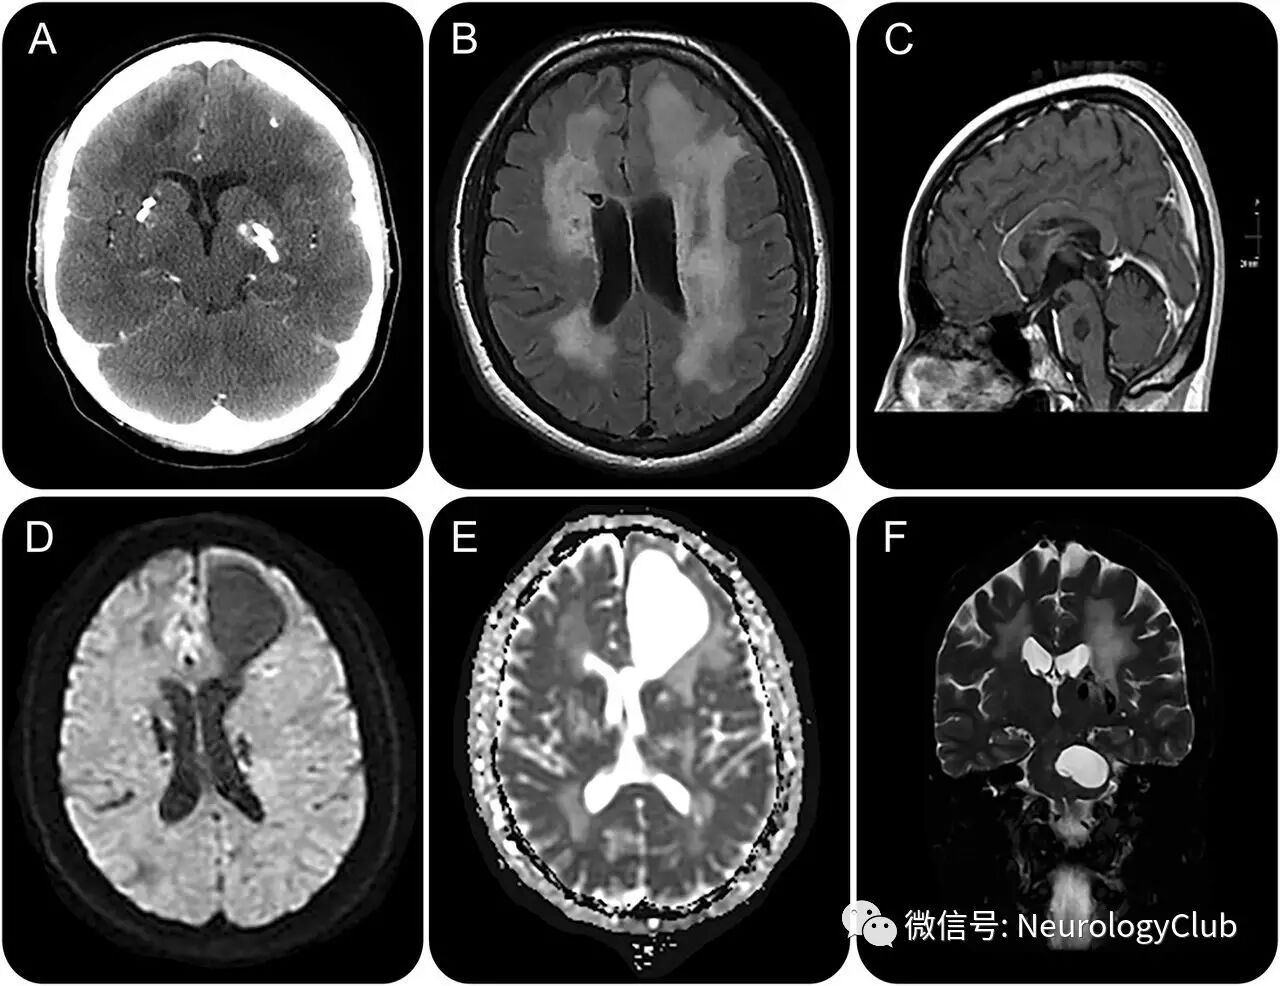

42岁女性,因复杂部分性发作入院。患者18岁时,曾有短暂复视,考虑为简单的斜视。本次查体提示左侧外展神经麻痹,右上肢反射亢进。神经影像学提示颅内白质多发囊性病灶(图),基底节区多发钙化,以及弥漫的双侧脑白质病变。

(图:A:CT提示基底节区[CT值1541HU豆状核],左侧丘脑和白质处散在钙化,额叶囊性变,以及白质弥漫低密度区;B:FLAIR可见广泛的白质病变;C:T1增强提示左侧脑桥囊性病灶无明显强化;D-E:DWI和ADC上囊性变有轻度占位效应,无血管源性水肿或弥散受限;F:T2WI可见左侧脑桥较大囊性病灶,白质病变明显)

伴钙化和囊变的脑白质病(Labrune综合征)

伴颅内钙化和囊变的脑白质病被认为是主要累及儿童的弥漫微血管病。成人起病的患者临床症状多样且通常较轻,进展缓慢。